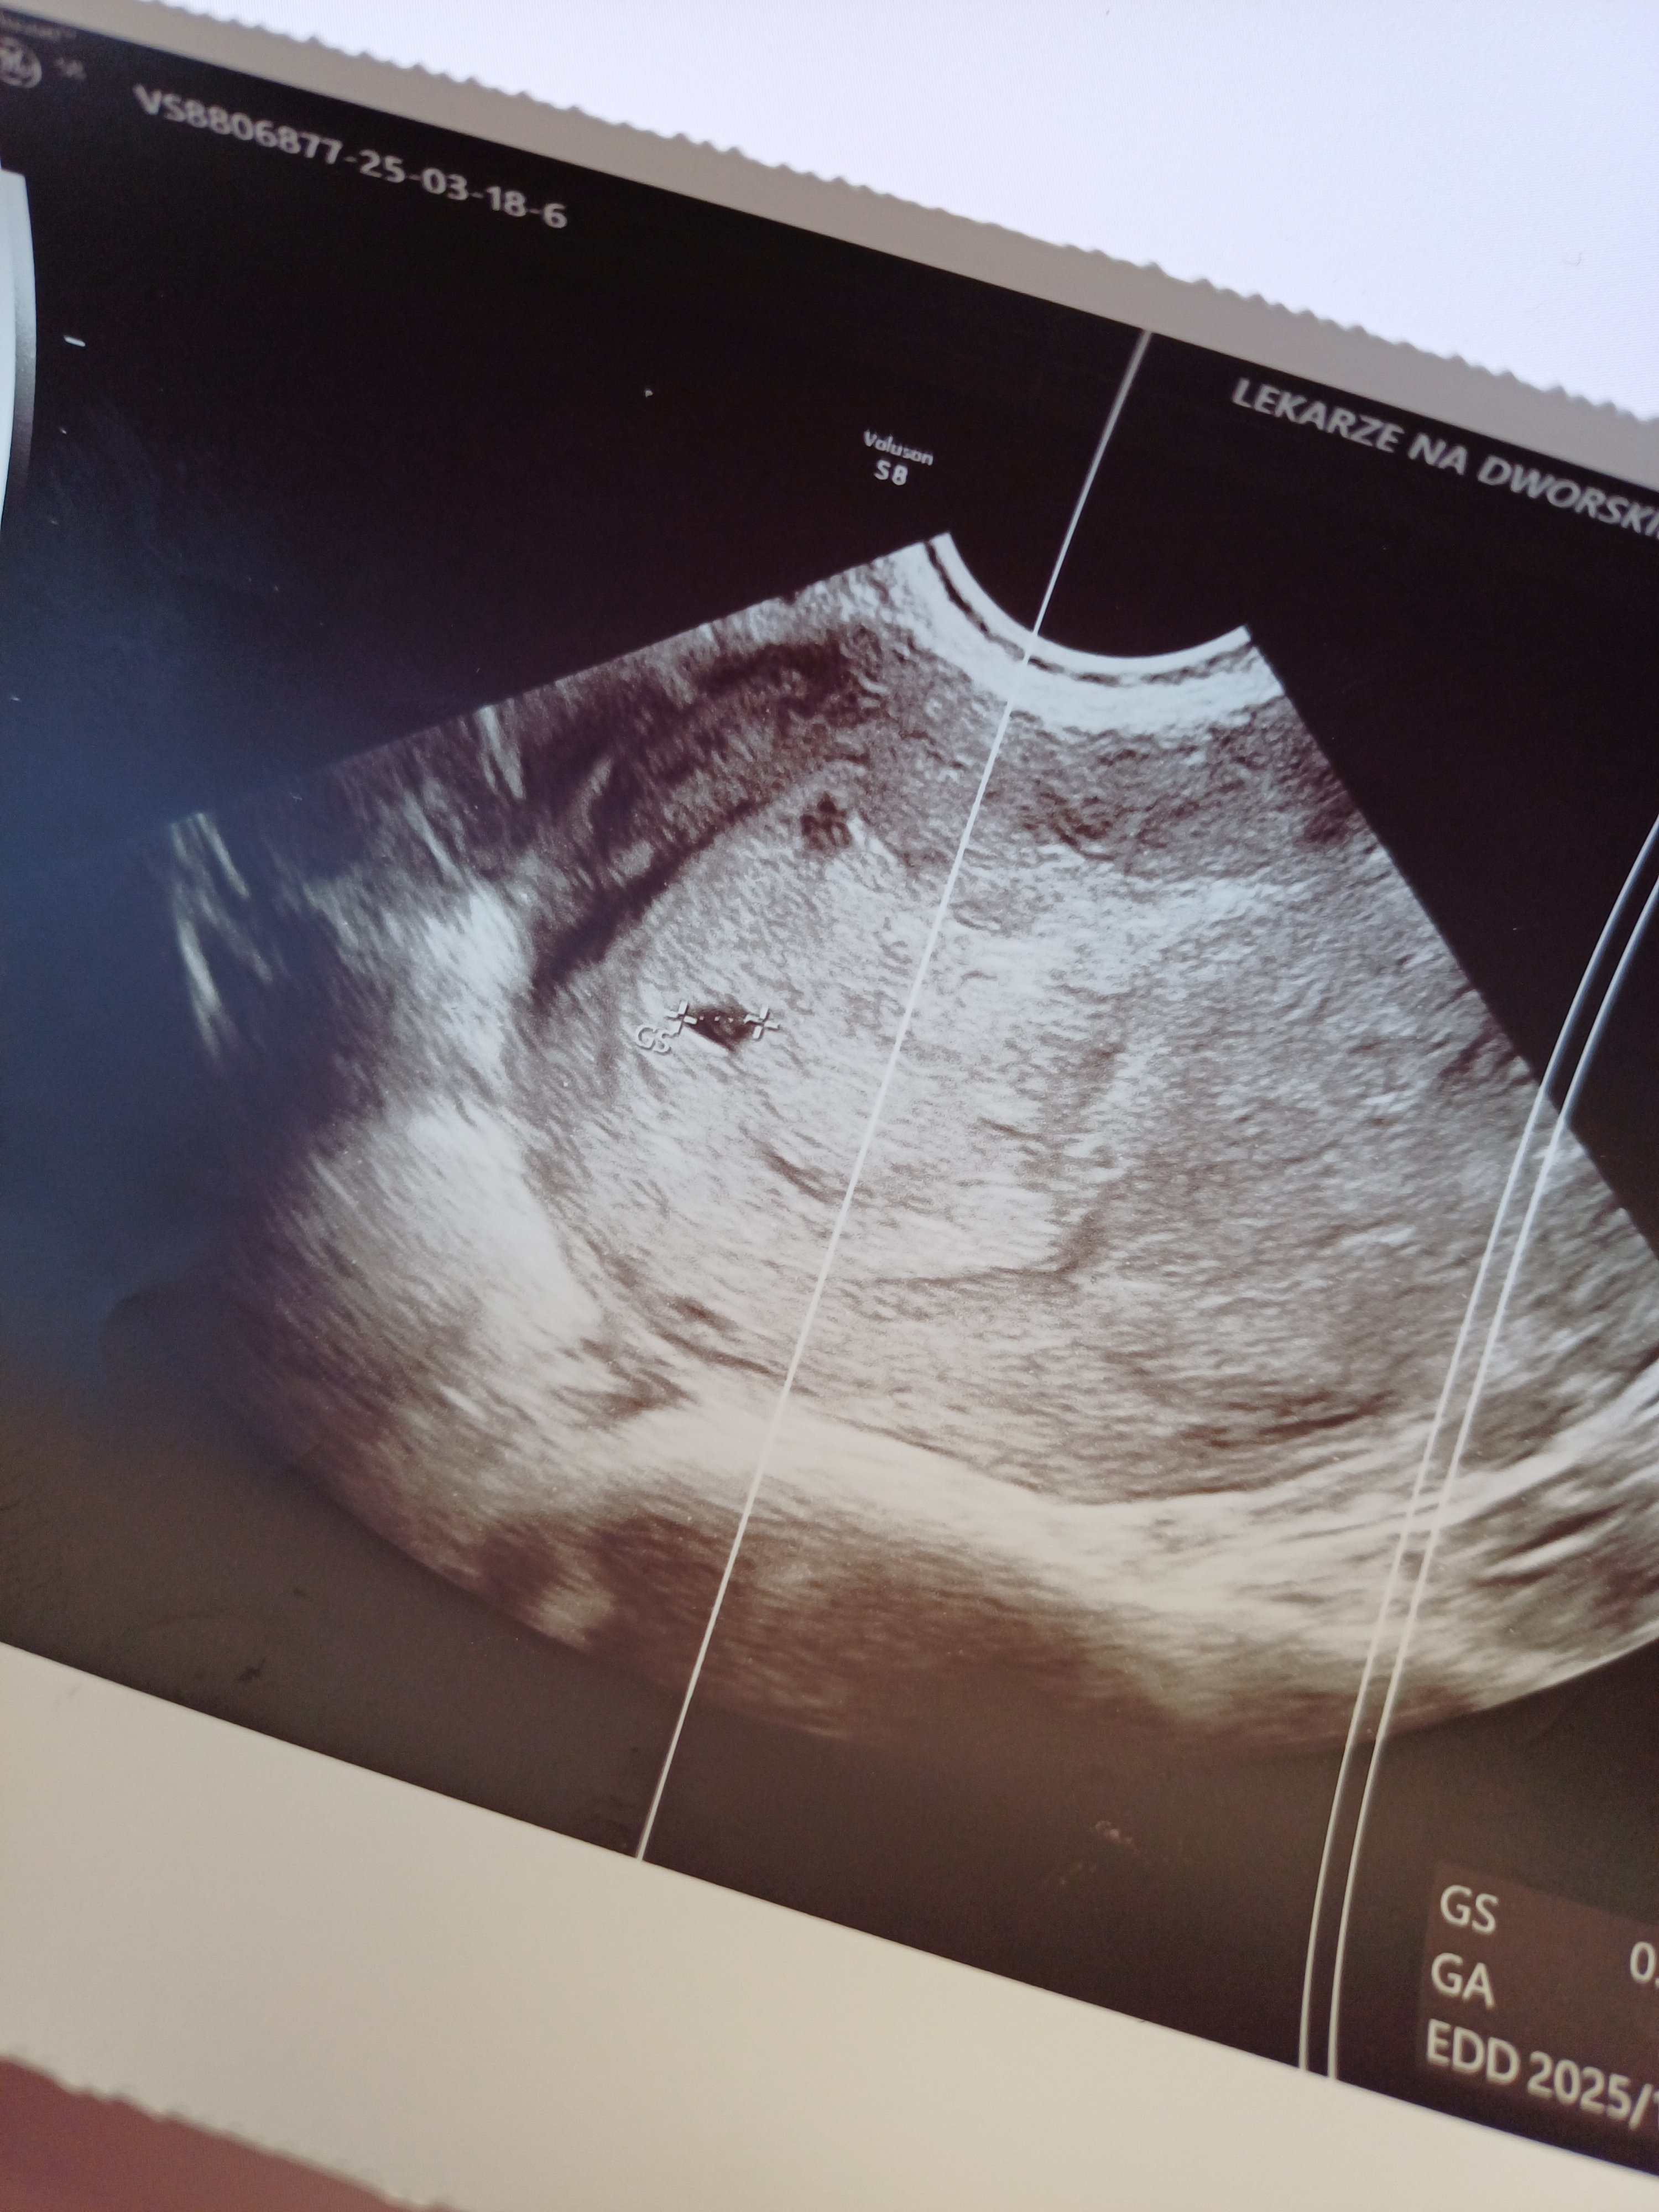

Jestem po pierwszym USG drugiej ciąży. Serduszko jeszcze nie biło, bo za wcześnie, 4-5 tydzień, ale po wyjściu po lekarza zaciekawiło mnie co to za drugi pęcherzyk? Czy to może oznaczać ciążę bliźniaczą? Czy może to coś innego pokazywać. Nie mam w rodzinie bliźniaków ani żadnych predyspozycji, ale natura zaskakuje